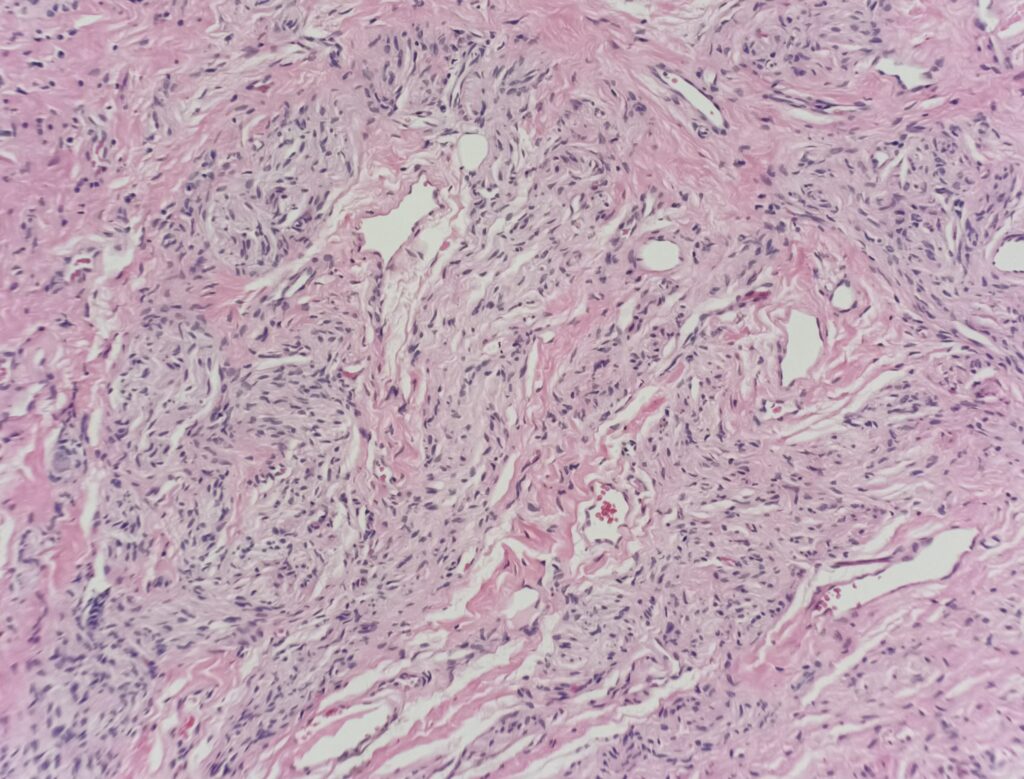

Histology:

Irritation fibroma – Benign reactive fibroblast proliferation that usually affects the lateral tongue and buccal mucosa. Histologic sections show a nodular, non-encapsulated proliferation of fibrous tissue with dense collagen bundles.